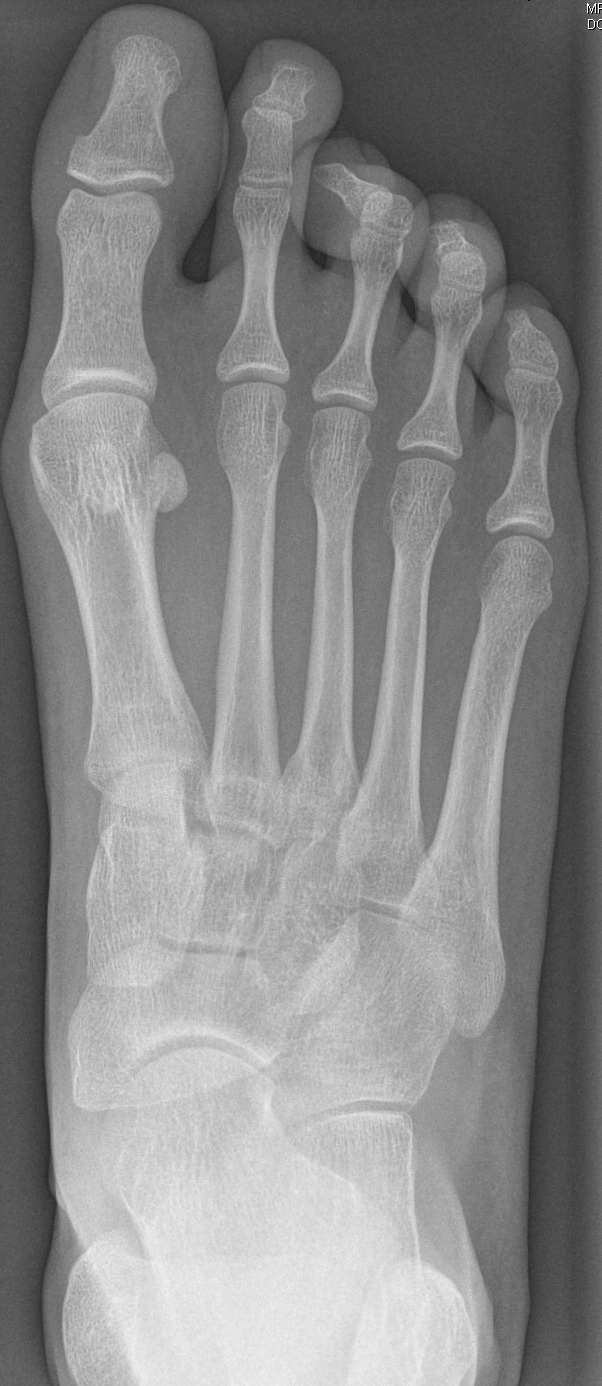

In der Regel bestehen aktive Wachstumsfugen bei Mädchen bis zum 12. und bei Jungen bis zum 14. Lebensjahr, mit Abweichungen von einem Jahr nach unten und nach oben. Präzise Informationen unter anderem darüber gibt das präoperative Röntgenbild (Abb. 2).

Abb. 2 a-c: offene Wachstumsfugen MT I Basis und Zehen (a), teilweise geöffnete Wachstumsfugen (b) und geschlossene Wachstumsfugen (c).

Zum Lesen der Bildbeschreibung und zur Vollansicht bitte die Bilder anklicken. Bilder: A. Helmers.